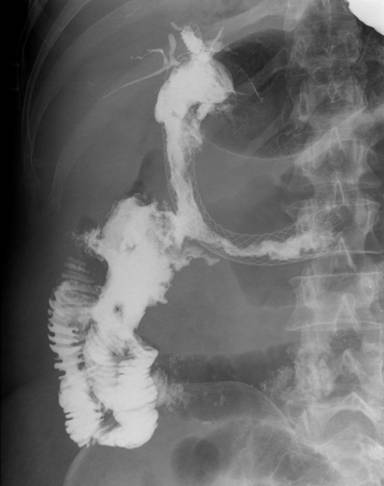

Deployment of both biliary and duodenal stents was technically successful in all cases. However, only three patients experienced relief of jaundice and gastric outlet obstruction. Of those patients, only two were discharged from the hospital. Three patients died from direct or indirect endosonography-guided biliary drainage related complications (Table 3).

Figure 8. Duodenoenteric fistula. |

Duodenoenteric

fistula 16 days after the procedure (Figure 8). |